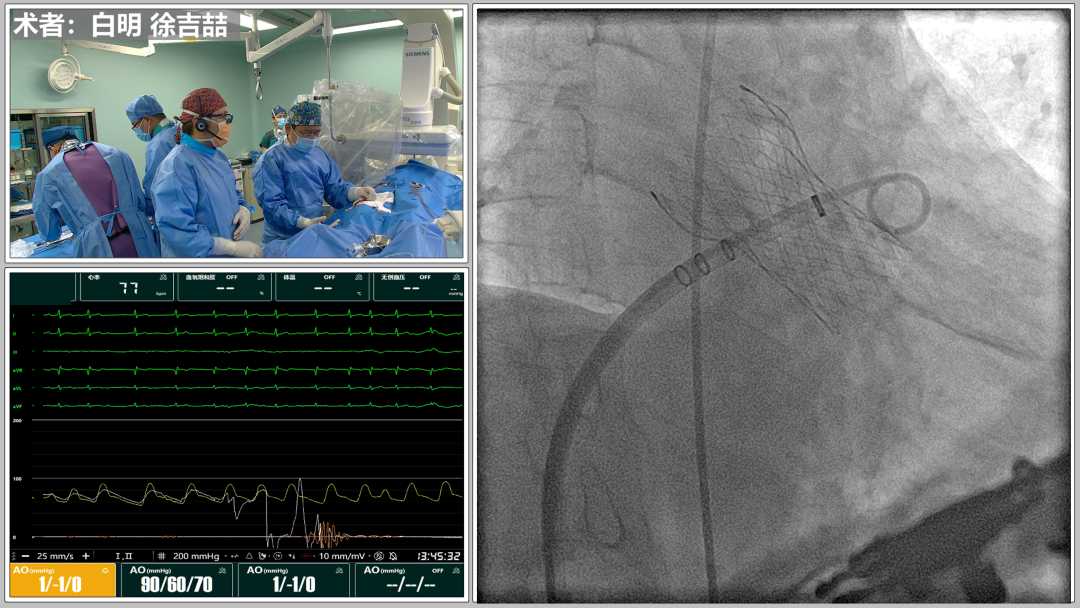

2022年5月13日,兰州大学第一医院心脏中心白明教授团队成功为一名高龄、重度主动脉瓣膜狭窄伴房颤心衰患者行经导管主动脉瓣膜置换(TAVR)和左心耳封堵(LAAC)手术,此例为甘肃地区首例TAVR+LAAC一站式手术,预示着甘肃地区结构性心脏病诊疗继续迈向新高度。

经各项术前诊断分析,白明教授充分评估后,决定行经导管主动脉瓣膜置换(TAVR)和左心耳封堵(LAAC)一站式手术彻底解决患者心脏结构问题,此手术难点突出:

预扩

猪尾中部释放

稳定回收

评估

最终释放

后扩

无瓣周漏